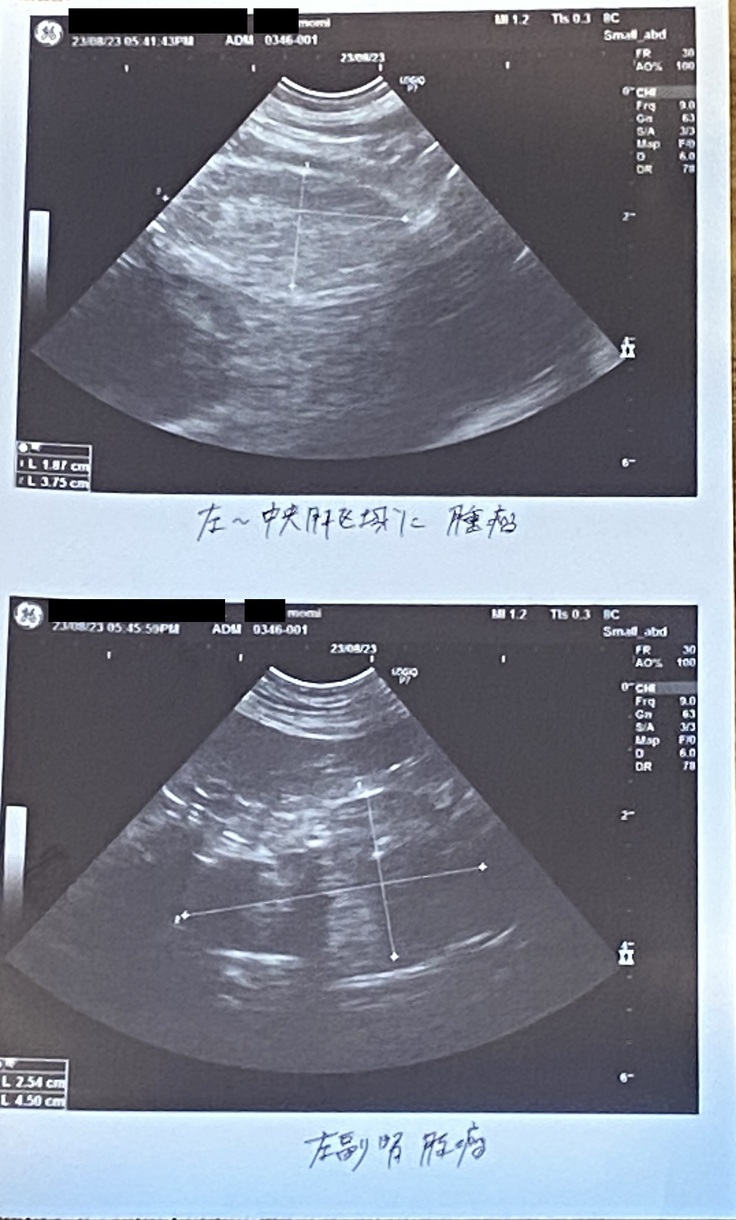

現在、肩にあった腫瘍は切除しましたが、副腎に腫瘍があります。

また、もみは今回の診断の際に副腎にも腫瘍らしきものがあることがわかっています。